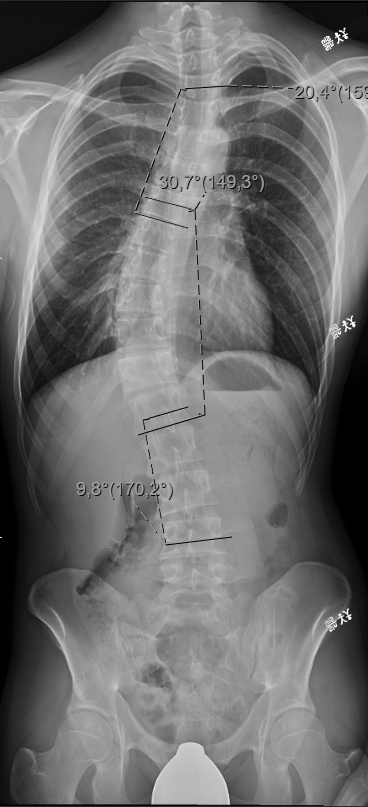

Functionally, not as bad as it looks. Just go gym and do physical therapy and live healthy and your chillin with, at worst, managable back pain when you get older. You only get bad back problems if your not taking care of it. It feels "almost" like having a normal back if you do take care of it.

Aesthetically though you are a bit cooked. Gymmax and you look good from front and 3/4 / sides but your back will obviously be lacking. Not the end of the world though as it still looks okay as long as you put on muscle.

Honestly, i feel as if the trade off is 100% worth it. I sometimes do get a bit insecure about my back but it is what it is. I can still have a good physique overall, and i would even say my back could be "somewhat" aesthetic if i just put on the muscle. Whatever is in charage of this world decided to give me height for a bad back, and honestly im thankful everyday. If your short and ever see a mfer with scoliosis thats tall complaining then shove your dick down his throat for being an ungrateful fuck (unless the mfer has like 90 degrees curve or some shit). This is highkirkuienly a shitpost ik but its 2am and i cant sleep and i was thinking about this